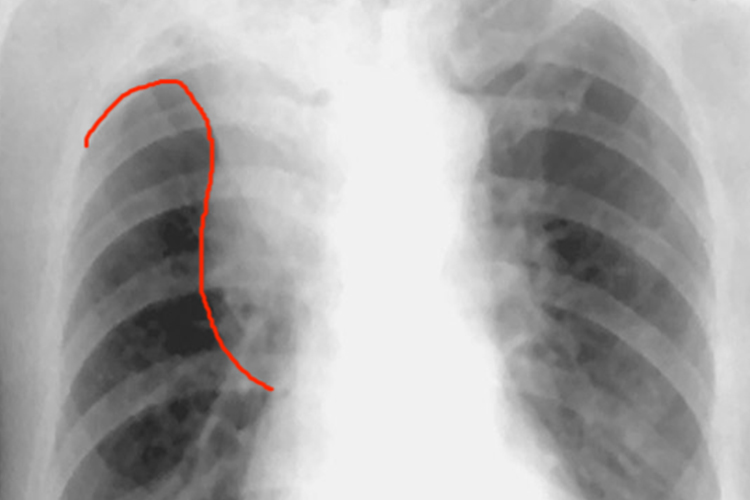

肺鳞癌又称肺鳞状上皮细胞癌,Ⅲ期已经处于晚期,会有明显的临床症状,如咳嗽、痰血或咯血、气短或喘息、胸痛、发热、全身消瘦等,当癌肿在较大的支气管内长大后,常出现刺激性咳嗽。肺鳞状上皮细胞癌常为中心型肺癌,X线胸片多表现为一侧肺门类圆形阴影,边缘毛糙,可有分叶或切迹,与肺不张或阻塞性肺炎并存时,下缘可表现为倒S状影像,是右上叶中央型肺癌的典型征象。